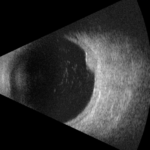

Figura 7. Angiografia al verde d’indocianina della lesione a circa 2 minuti dall’iniezione del colorante.